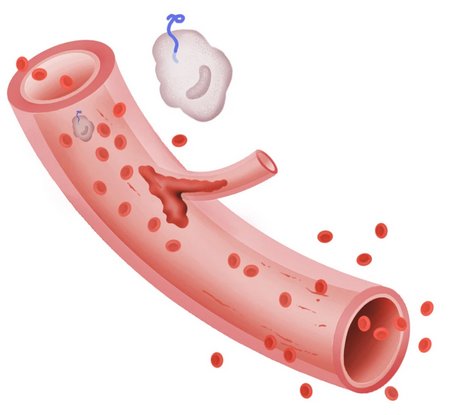

مشکل در جریان خون

پروتئین های منتشر شده توسط سلول های ایمنی، التهاب گسترده ای را ایجاد می کنند. این التهاب می تواند به پوشش بافت رگ های خونی آسیب رسانده و باعث نشت آنها شود.

هنگامی که سلول های ایمنی شناخته شده به عنوان ماکروفاژها توسط ابولا مورد حمله قرار می گیرند، پروتئین ها را آزاد می کنند که این موضوع باعث انعقاد در جریان خون و انسداد جریان خون در بافت هایی از جمله کبد، مغز و کلیه ها می شود. هنگامی که سلول های قرمز خون درون عروق کوچکی که از لخته پر شده اند حرکت می کنند، از هم گسسته شده و طحال از رگ های خونی شکسته شده، پوشیده می شود.

هنگامی که سلول ها در کبد از بین می روند، خون توانایی طبیعی خود را برای لخته شدن از دست می دهد و هر گونه خونریزی داخلی یا خارجی را تشدید می کند.